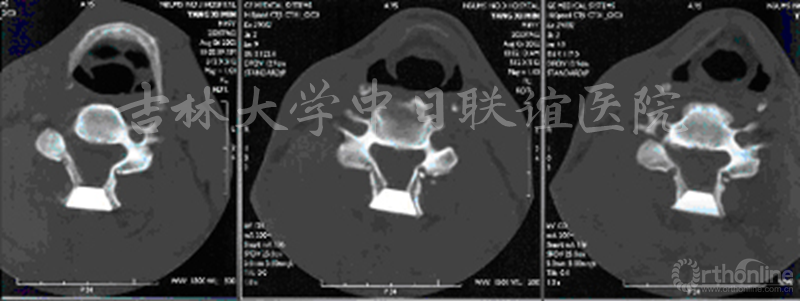

图4 术前、术后CT显示的椎管开大效果对比

男性患者,诊断为“发育性椎管狭窄伴无骨折脱位型颈脊髓损伤”,行C3-6后路双开门椎管扩大成形术。

患者术前术后影像学资料